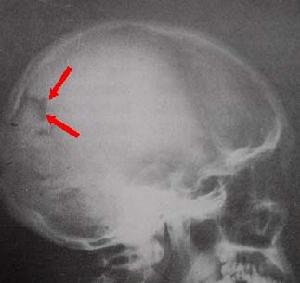

颅骨骨髓炎--X线拍片1.全身感染症状:畏寒、发热、困倦、四肢骨关节酸痛、食欲不振、精神萎糜等毒血症症状。身体其他部位有感染病源存在。 医学百科网 | YxBaike.Com

3.头部X线拍片:早期可无变化,亚急性与慢性期显示骨质破坏,死骨形成或增生硬化等骨质征象。